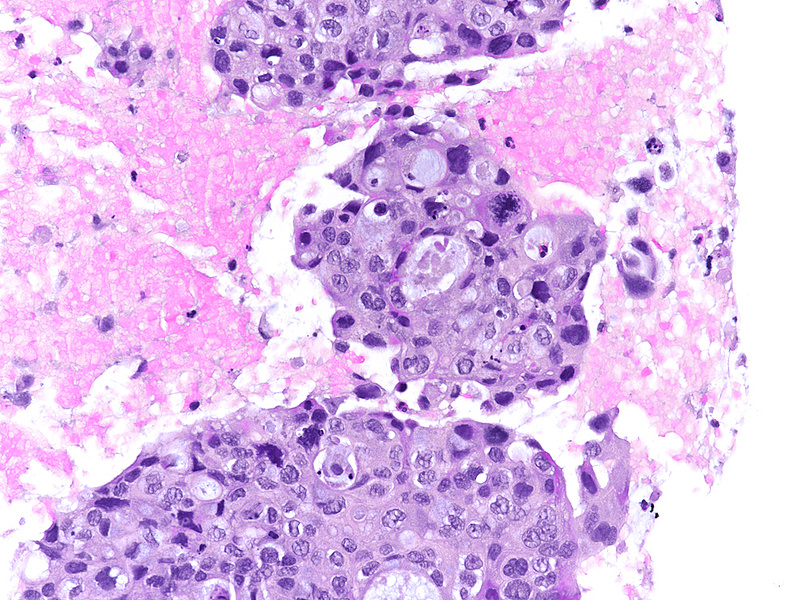

The well-sampled biopsy showed fragments of a necrotising carcinoma, arranged in isolated cells, small aggregates of cells and poorly formed glandular structures (Panels A-B). The tumour cells demonstrated abundant eosinophilic cytoplasm and severely pleomorphic, hyperchromatic nuclei with distinct nucleoli. Brisk mitotic activity was noted (Panel C). Within some clusters, the neoplastic cells had a more polygonal appearance, with intercellular desmosomes, more basophilic cytoplasm and evidence of dyskeratosis (Panels D-E).

By immunohistochemistry, the tumour cells were strongly and diffusely positive for CK7 (Panel F), focally positive also for p40 (Panel G) and CK20 (not shown). Ki67 labelling index confirmed the suspected high proliferation rate, estimated between 40-50% (Panel H). The immunohistochemical screening for DNA mismatch repair (MMR) deficiency showed no loss of protein expression. A final diagnosis of poorly (to undifferentiated) adenocarcinoma of the pancreas with squamous differentiation (consistent with adenosquamous carcinoma) was made.